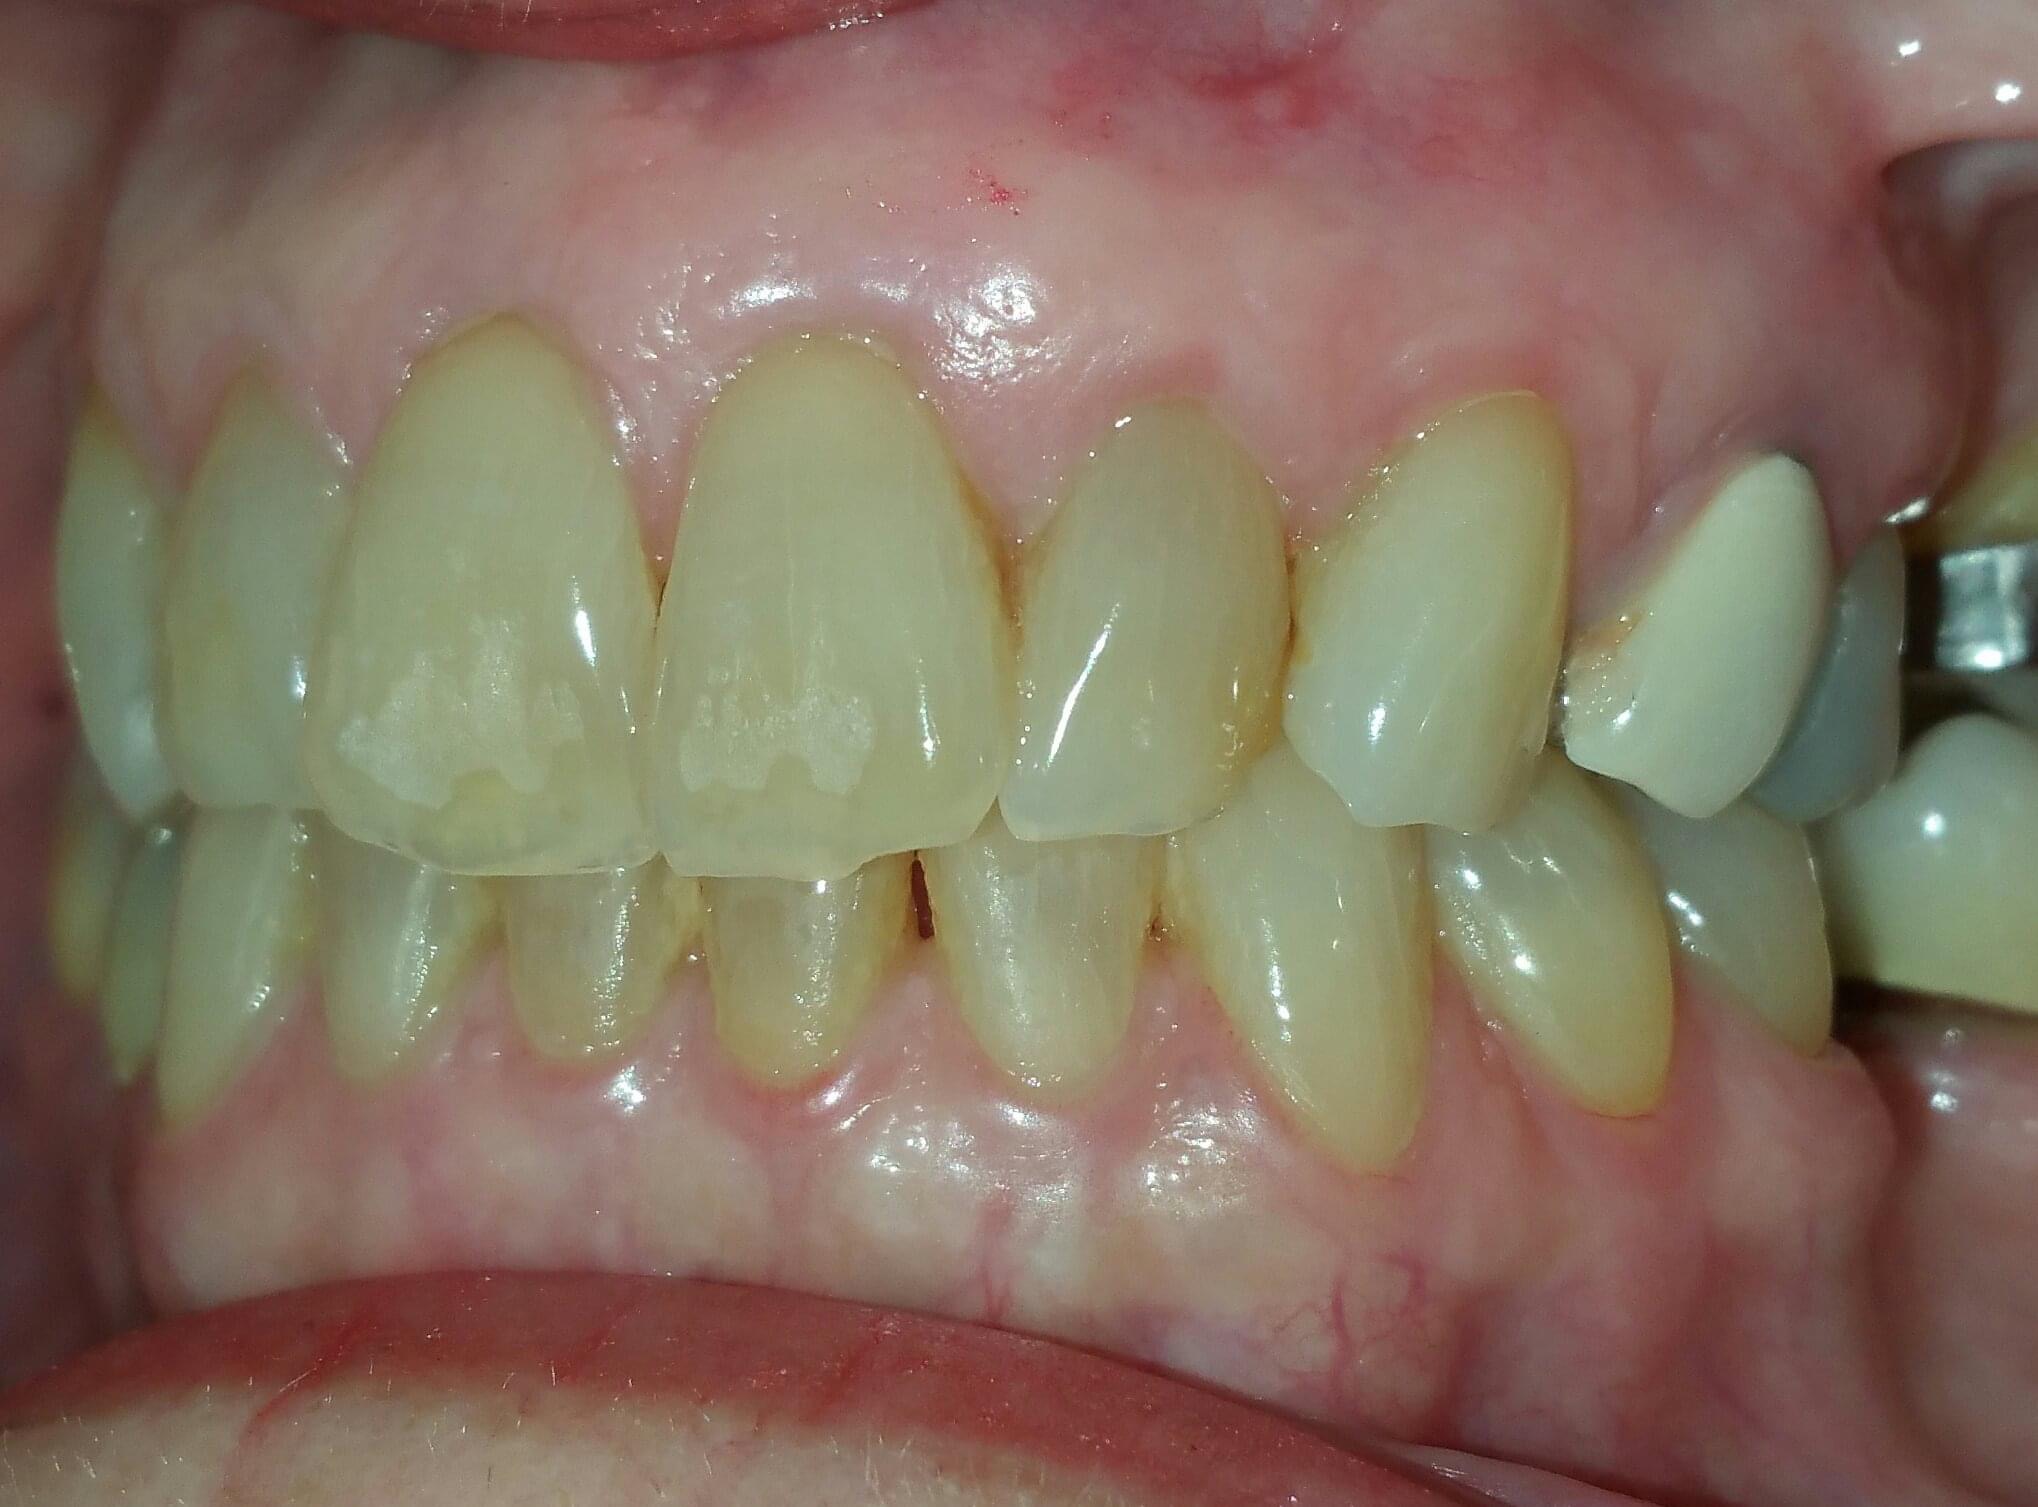

BEFORE AND AFTER PICTURES: